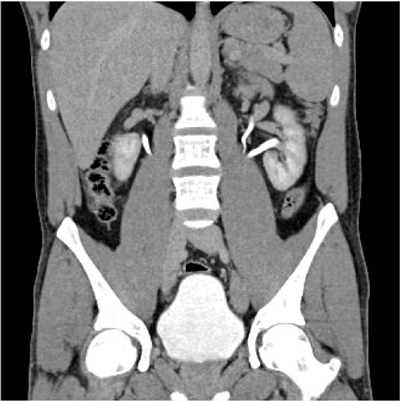

Horseshoe kidney

A horseshoe kidney (Figure 1) is a congenital anomaly in which kidneys are fused by the isthmus at the lower poles. In 90% of cases this is a midline, or symmetrical fusion, but lateral fusion is also a variant. The axis of each renal pelvis remains vertical or in the obliquely lateral plane, and the calyces point posteriorly. The horseshoe kidney lies ectopically with the isthmus located adjacent to the L3 to L4 level. This is due to the inferior mesenteric artery preventing further ascent as it crosses the isthmus. Approximately one third of horseshoe kidneys have a single renal artery to each renal pelvis, whereas the remainder have a variable blood supply [1].

The incidence is 1 in 400 and it is the commonest renal fusion anomaly. There is a male predominance with male to female ratio 2:1. It is often asymptomatic, but patients may present with vague abdominal pain, radiating to the back, ureteral obstruction, or palpable midline abdominal mass. Approximately 50% of horseshoe kidneys have associated vesicoureteral reflux and 30% of patients develop urinary tract infections [1]. Horseshoe kidneys have increased risk of traumatic injury, due to the isthmus lying anteriorly without the protection of the ribs, and it can be split by high impact blunt abdominal trauma [2].

On the plain abdomen film the lower poles of the kidneys are seen medial to the upper poles, in contrast with normal renal anatomy where lower poles are lateral. Ultrasound may reveal the isthmus lying anterior to the spine and contiguous with the lower poles of both kidneys. However due to the positioning of bowel gas centrally, the isthmus may not be clearly viewed and appearances may be of a curved configuration to the kidneys with poorly defined lower poles. In the longitudinal plane the kidneys may appear as an inverted triangular or pyriform shape [3,4]. Contrast enhanced CT will provide the clearest imaging, and helps to define the structural abnormalities of the horseshoe kidney. On CT the following questions can be answered: the degree and site of the fusion, degree of renal malrotation, any associated collecting system abnormalities, and any renal parenchymal changes. CT enables differentiation between normal and fibrous parenchyma within the isthmus, which is almost always functioning tissue.

CT angiography is useful in evaluating arterial anatomy as horseshoe kidneys often have variant arterial supply, including multiple renal arteries, arteries arising from aorta or common, internal or external iliac, or inferior mesenteric arteries [5]. Nuclear medicine imaging can demonstrate fusion with functional parenchymal tissue, and can detect regional loss of function due to obstruction and inflammation [3].